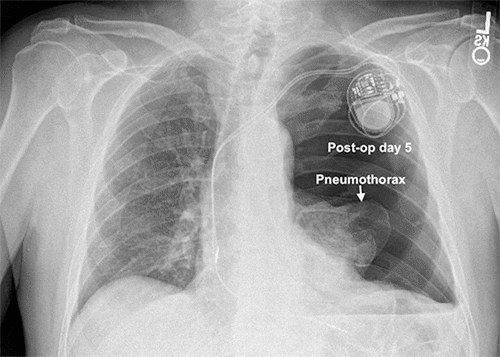

Figure 3. Resolution of PTX After Left Chest Tube Placement. Published with Permission

Right ventricular (RV) pacemaker lead has changed position compared to immediate postoperative CXR five days prior.

The patient's dyspnea resolved, but he developed the same type of heart palpitations and dizziness that he had been experiencing before his pacemaker. His pacemaker was interrogated, and it was not possible to stimulate the ventricular lead, suggesting that the lead was free-floating in the ventricle. We concluded that the lead had been pulled out by the rapid reversal of his mediastinal shift after placing the chest tube. The patient was brought back to the operating room the next day to reposition the lead into the myocardium of the apical septum of the RV. His chest tube was water sealed and removed the following day. We had him use his CPAP overnight and confirmed no PTX 24 hours after chest tube removal. He was discharged home in stable condition and was doing well with no recurrent PTX at follow-up a week later.